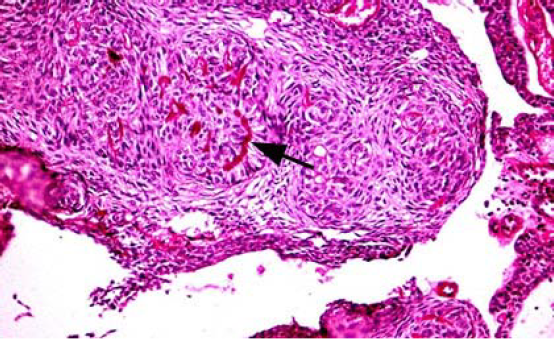

Microscópicamente, a pequeño aumento el patrón histomorfológico más destacado está dado por la presencia de nódulos de tamaños variados, compuestos por células cuboidales o columnares de epitelio odontogénico, formando nidos o estructuras en forma de "rosetas" con poco estroma de tejido conectivo. Entre estas células y en el centro de las rosetas se observa el depósito de un material eosinofílico amorfo PAS positivo (gotas tumorales) (Fig. 1 y Fig. 2).

Dentro de estas áreas celulares pueden observarse o no, estructuras tubulares con aspecto de seudo-conductos, revestidos de una hilera simple de células epiteliales columnares con el núcleo polarizado hacia la capa basal, y la luz de estos puede encontrarse vacía o contener un material eosinofílico o restos celulares. Adicionalmente, las células columnares pueden formar cordones en patrones complicados que a menudo exhiben invaginaciones. Otro patrón celular característico está dado por la presencia de nódulos formados por células poliédricas eosinofílicas, de aspecto escamoso con bordes bien definidos y puentes intercelulares prominentes. Los núcleos, en ocasiones, pueden exhibir ligero pleomorfismo (de origen degenerativo). Estos nódulos pueden contener agrupaciones de material amiloideo y masas de calcificación distrófica. El estroma conectivo contiene vasos sanguíneos de paredes delgadas (Fig. 3). Pueden verse áreas microquísticas.